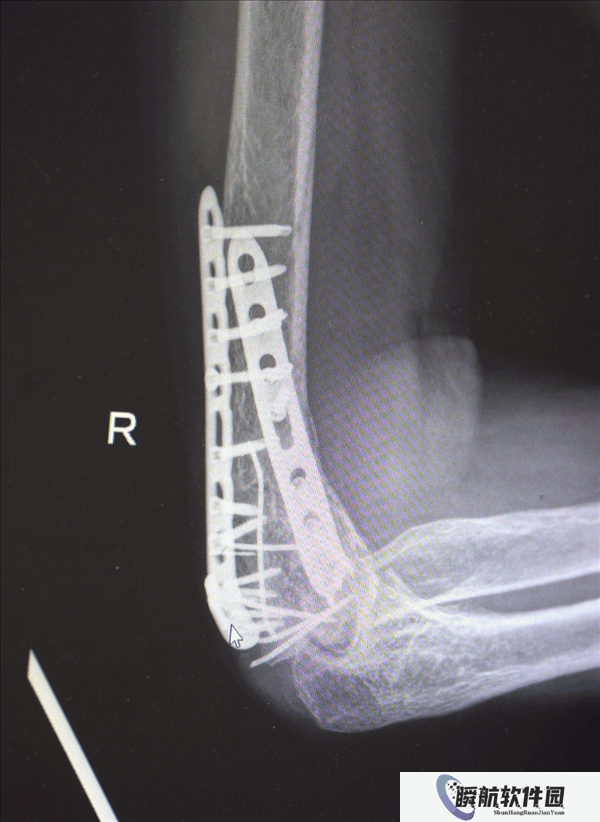

鉴于男子多处骨折,其中最严重的当属右肘部C3型粉碎性骨折,关节面及髁上严重粉碎(碎成了七块),肘关节易粘连,复位固定难度极高。

最终医疗团队采用了“拼古董”式复位固定技术,就像修复一件珍贵的古董瓷器,先拼接大块骨块再贴合小块,先后进行了两次手术。